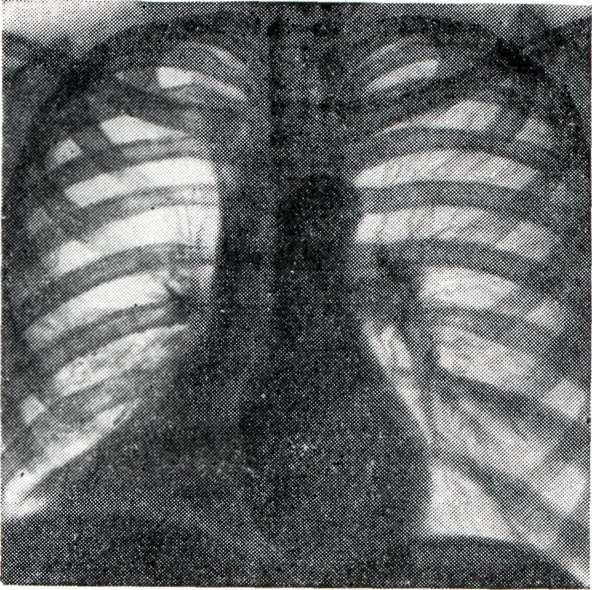

При тотальном ателектазе (рис. 3, 1 и 2) спавшееся легкое обычно уменьшено, интенсивно и равномерно затемнено. В большинстве случаев тени ребер сближены (соответственно западению грудной стенки), иногда наблюдается сколиоз грудного отдела позвоночника, выпуклостью обращенный в сторону поражения. Купол диафрагмы и тени поддиафрагмальных органов на стороне ателектаза приподняты; слева необычно высоко и медиально проецируется газовый желудочный пузырь. Срединная тень, в частности трахея, значительно перетянута в сторону ателектаза, бифуркация трахеи проецируется сбоку от тени позвоночника. Непораженное второе легкое вздуто, и его тень частично перемещена в противоположную половину грудной клетки. Такое перемещение испытывают главным образом передне-верхние позадигрудинные отделы противоположного легкого, давая в рентгенологическом отображении картину так называемой медиастинальной грыжи, то есть ограниченное дугообразной линией просветление на фоне верхне-медиальных отделов затемненного легочного поля на стороне ателектаза. Такие «грыжи» могут достигать больших размеров, в особенности при ателектазе левого легкого. Рентгенологическая картина при долевых ателектазах типична (рис. 3, 3—12). Как известно, доли легких как бы фиксированы в двух местах: у корня и из-за отрицательного внутриплеврального давления у грудной стенки. В силу эти особенностей спадение и перемещение долей легких при ателектазе происходит в случае отсутствия плевральных сращений закономерно в определенном направлении. Верхняя доля правого легкого смещается при ателектазе кверху, кнутри и кпереди в направлении передне-медиальных отделов грудной клетки. Нижняя граница тени спавшейся доли (линия малой междолевой щели) перемещается кверху, задняя (линия главной междолевой щели) — кпереди. На боковой рентгенограмме определяется треугольная тень с несколько втянутыми гладкими контурами, вершина которой примыкает к тени корня, а основание — к грудной стенке. На фоне этой тени хорошо видна линия косой междолевой щели, переместившейся кпереди. При нарастающем спадении доли последняя приближается к грудной стенке и исчезает. Спадение верхней доли может быть столь значительным, что на прямой рентгенограмме ее тень представляется узкой боковой полоской у средостения, а в боковой проекции — симулирует уплотнение легочного сегмента. Ателектаз верхней доли сопровождается расширением нижней и средней долей, наибольшему вздутию подвергаются задне-верхние отделы нижней и верхне-передние отделы средней доли. Тень корня легкого перемещается, как правило, кверху. При ателектазе правой верхней доли, как и при ателектазах других долей, наблюдаются и атипичные картины, нередко симулирующие на передней рентгенограмме картину медиастинальной «грыжи», что обусловлено главным образом плевральными сращениями, фиксирующими легкое. Рентгенологическая картина ателектаза верхней доли левого легкого отличается большим объемом, более отвесным расположением левой косой междолевой щели и не всегда четкой нижней границей тени: в части случаев она дугообразно втянута. Средняя доля при ателектазе смещается кнутри и кпереди. Верхняя граница ее перемещается книзу, нижняя, соответствующая косой междолевой щели, — кверху и несколько кпереди. На прямой рентгенограмме спавшаяся доля проецируется в нижне-медиальных отделах легочного поля; тень ее обычно треугольной формы, имеет вогнутые верхний и нижний контуры или же втянутый или прямолинейный нижний и слегка выпуклый верхний контур. В боковой проекции тень имеет также форму треугольника с ровными и чаще втянутыми контурами либо форму полосы, овала, полуовала с выпуклой верхней и прямолинейной или втянутой нижней границей. При резком уменьшении средней доли она может быть представлена на прямой рентгенограмме нехарактерным малоинтенсивным затемнением, и лишь исследование в боковом или лордотическом положении позволяет выявить тень, характерную для ателектаза средней доли. Тень корня перемещается обычно книзу. Нижние доли обоих легких смещаются при ателектазе книзу, кнутри и кзади. На прямой рентгенограмме уменьшенная доля имеет форму треугольной тени, вершиной обращенной к корню и основанием к диафрагме. Наружная граница тени несколько втянута, иногда — выпуклая или прямолинейная. При большом уменьшении доли определяется небольших размеров треугольная тень у контура позвоночника, которая может быть перекрыта слева тенью сердца. В боковой проекции тень спавшейся доли частично наслаивается на тень позвоночника; видна линия переместившейся кзади косой междолевой щели. Спадение нижней доли сопровождается вздутием верхней, а справа — и средней доли; тень корня смещается книзу и кнутри. Сегментарный ателектаз имеет менее характерную рентгенологическую картину, тень его нередко симулирует картину сегментарного уплотнения воспалительной природы. Вторичные симптомы обычно не выражены. Как правило, сегментарный ателектаз не вызывает западения грудной стенки и изменений противоположного легкого. Обычно спадение сегмента сопровождается перемещением лишь граничащих с ним отрезков междолевых щелей, вздутием соседних отделов легкого. Симптом Гольцкнехта — Якобсона при сегментарном ателектазе выражен недостаточно отчетливо. Иногда диагноз может быть установлен лишь с помощью томо¬графии или бронхографии. Рентгенологическая картина ателектаза отдельных сегментов легкого представлена на схеме (рис. 4). Дольковые и ацинозные ателектазы обычно бывают множественными. Рентгенологически они не отличимы от теней очаговой пневмонии, с которой нередко сочетаются. При большом числе дольковых ателектазов, занимающих большую часть легкого, наблюдаются вторичные симптомы ателектаза, в частности положительный симптом Гольцкнехта—Якобсона. Дисковидные, или пластинчатые, ателектазы, расположены обычно низко над диафрагмой; рентгенологически имеют форму поперечно расположенных полосовидных теней (рис. 5) шириной существовании дисковидного ателектаза соответствующий участок легкого может подвергнуться рубцовому превращению.